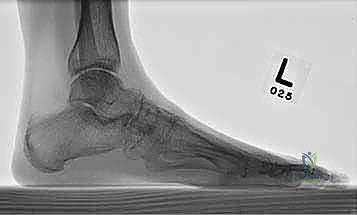

- الأشعة السينية أثناء الوقوف (Weight-bearing X-rays): وهي أهم أداة تشخيصية. الأشعة العادية والسرير فارغ لا تظهر المشكلة الحقيقية؛ يجب التقاط الأشعة والمريض يقف ليتحمل وزن الجسم، مما يظهر الانهيار الفعلي للمفاصل وتضيق المسافات بين العظام.

- الأشعة المقطعية (CT Scan): توفر صوراً ثلاثية الأبعاد للعظام، وهي ضرورية جداً للتخطيط الجراحي الدقيق وتحديد مدى التلف العظمي والزوايا المطلوبة للتثبيت.